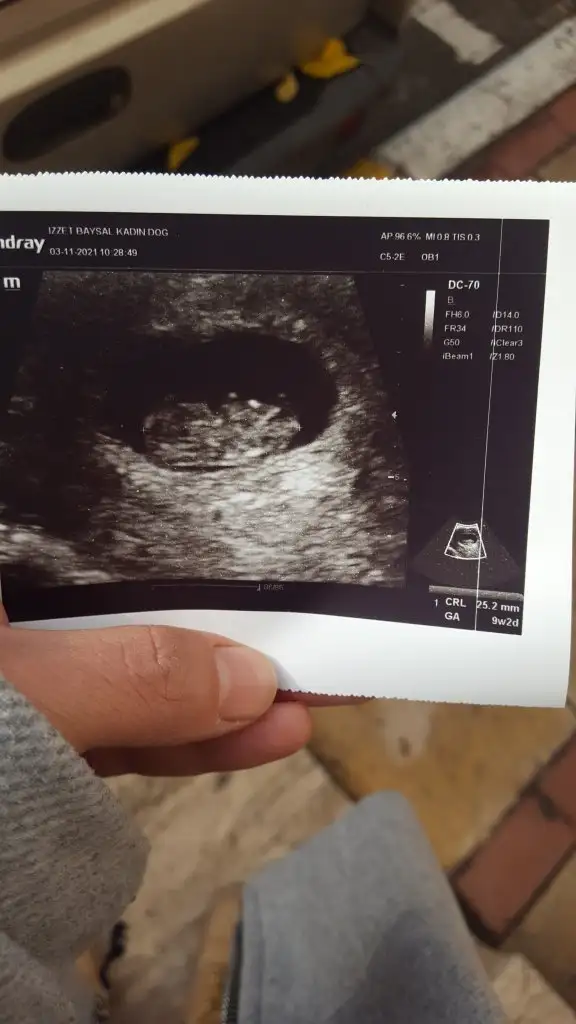

Tatlı yedim gitmeden çocuğum resmen halay çekiyordu🎈🙏😍😘😘 bunu buldum

Selam kızlar bugün gittim kontrole bebişimi detaylı şekilde gördük çok şükür ablası geldi diye show yaptı deli baklam kıpır kıpırdı çok şükür elhamdülillah rabbim sağlık versin tüm evlatlarımıza progestana devam tabii :KK200::dua:cinsiyet tahmini varmıı:nazar::anneadayı::anne:

Oyy maşallah çok şükür canım ne güzel gözüküyor demi kıpır kıpır oynaması 🥰bende çok şaşırmıştım 9 haftada görünce